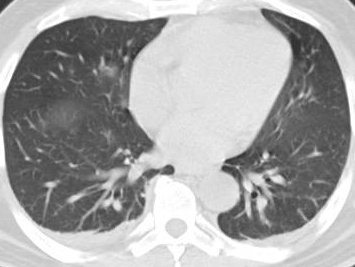

İnönü Üniversitesi Tıp Fakültesi Biyoistatistik ve Tıp Bilişimi Anabilim Dalı tarafından tasarlanan açık kaynak erişimli yapay zekâ tabanlı yazılım prototiplemesi ile covid-19 tanısında hekimlere klinik destek sağlayabilecek bir modelin geliştirilmesi hedeflenmektedir.

Toraks (göğüs) Bilgisayarlı Tomografi (BT)

cihazlarından alınan görüntüler kullanılarak derin öğrenme ve görüntü işleme tabanlı bir model oluşturulmuştur. Tasarlanan bu eğitilmiş model sayesinde covid-19 sınıflandırılması geliştirilen web tabanlı yazılım prototiplemesi ile yapılabilmektedir.